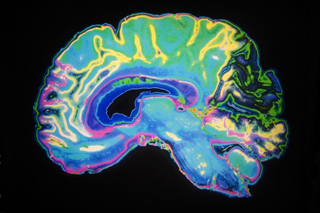

Cei zece pacienţi care au luat parte la studiu sufereau deja de Alzheimer sau de una dintre formele sale, precum deteriorare cognitivă minoră sau deteriorare cognitivă subiectivă. După administrarea tratamentului, majoritatea nu se mai încadrau în criteriile de diagnosticare a bolii. De exemplu, unul dintre pacienţi, în jurul vârstei de 60 de ani, suferea de reducerea unei părţi a creierului, numită hipocampus, având şanse de recuperare de 17%. După zece luni de tratament, radiografiile au arătat că volumul hipocampusului a crescut cu 75 de procente, fapt ce conincide cu o îmbunătăţire majoră a capacităţilor sale cognitive.